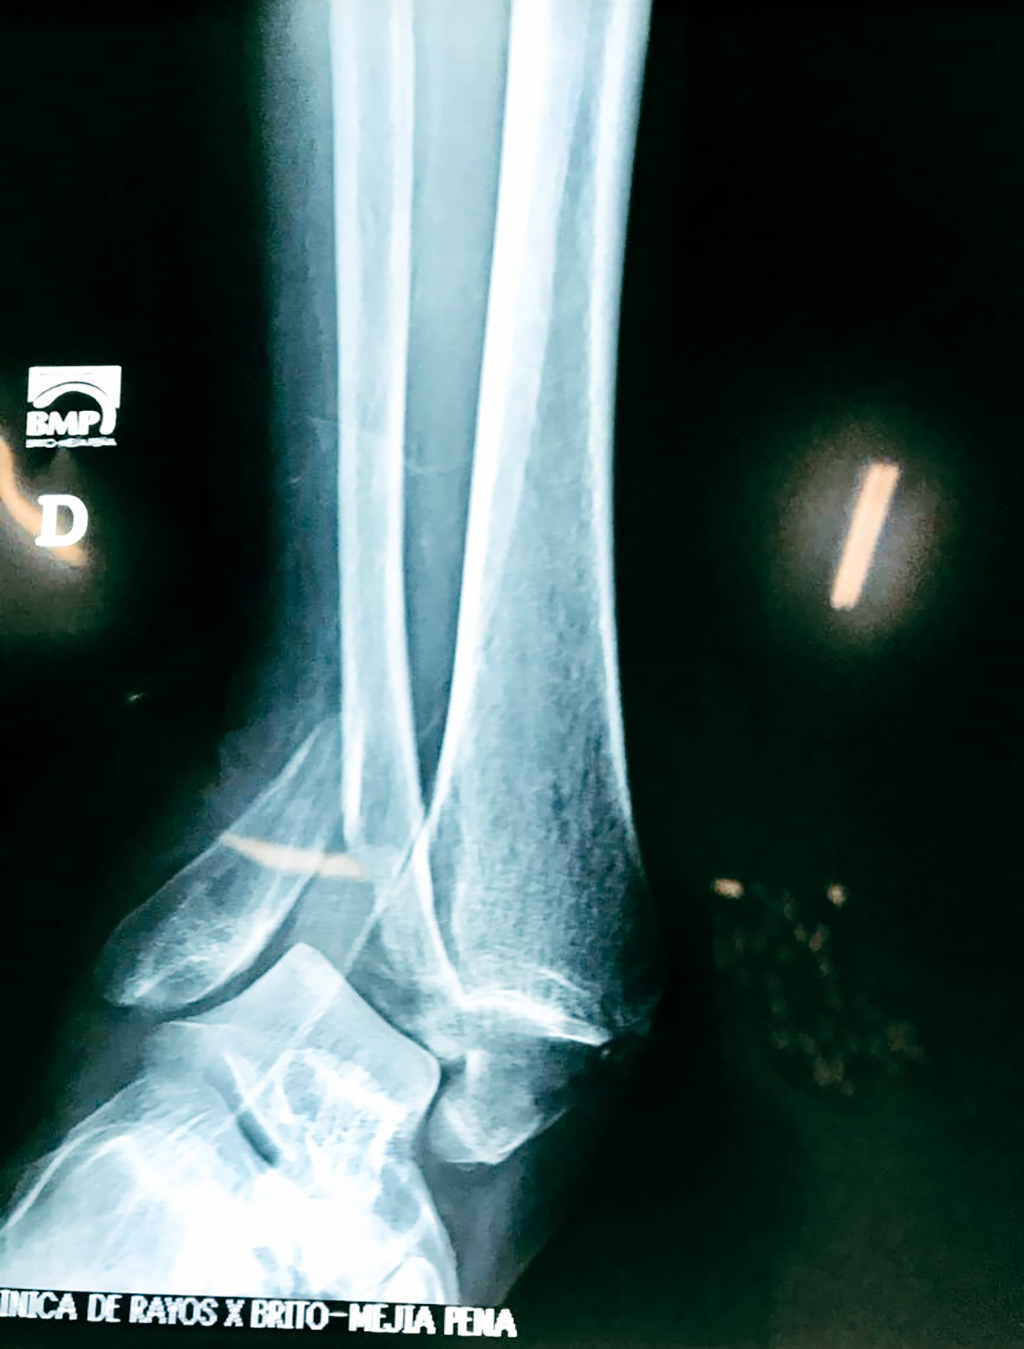

Una fractura de tobillo es la rotura de uno o más de los huesos del tobillo. Estas fracturas pueden ser:

- Producirse en uno o ambos lados del tobillo.

- Los extremos de los huesos están desalineados entre sí (desplazados).

- La fractura se extiende hasta la articulación del tobillo (fractura intra-articular).